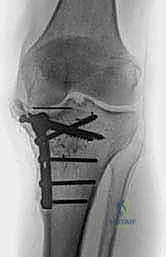

الدليل المصور: خطوات جراحة استبدال مفصل الركبة الكلي بالإسمنت خطوة بخطوة

تُعد هذه الجراحة عملاً فنياً هندسياً ودقيقاً، يتطلب مهارة جراحية استثنائية. بفضل تقنيات الجراحة المجهرية واستخدام أحدث الأدوات، يضمن الأستاذ الدكتور محمد هطيف دقة متناهية في كل خطوة. نستعرض هنا توثيقاً دقيقاً من داخل غرفة العمليات (Intraoperative Steps):

4. التجربة المبدئية وضبط توازن الأربطة (Trial Reduction)

قبل وضع الإسمنت والمفصل النهائي، يضع الجراح مفاصل تجريبية (Trials) لاختبار حركة الركبة، والتأكد من استقامة الساق، وتوازن الأربطة الجانبية في حالات الانثناء والانبساط.